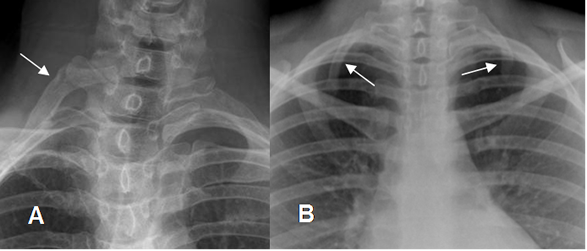

4. Costillas del cuello

Un conjunto de costillas que encontramos en la zona del cuello (marcadas con flechas), que posiblemente sean restos de la edad de los reptiles. Aparecen únicamente en el 1% de la población y, a menudo, causan problemas en los nervios y las arterias.